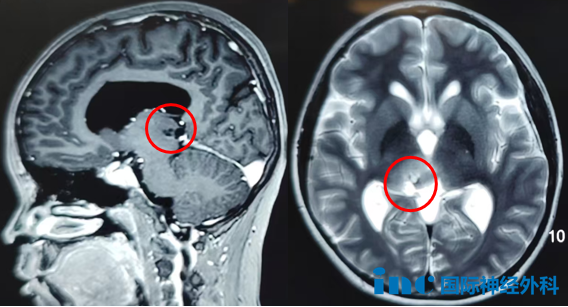

37岁女性丘脑海绵状血管瘤

37岁的思睿,在大家眼中一直是“温暖的小太阳”。2018年,丘脑出血导致思睿复视、记忆障碍、左半身偏瘫,连简单的抓握都成了奢望。医生坦言:“手术风险太大,后遗症可能比现在更严重。”无奈选择保守治疗,直到第2次出血,只能卧床休息时,她感到后怕——“之前是我太轻视了!”最终巴教授为她顺利全切丘脑-中脑海绵状血管瘤,术后第1天四肢活动正常、术前症状缓解。

术后1年,最新核磁显示海绵状血管瘤已被完整切除!视频中她的整体临床状态非常好。巴教授表示在经历过如此巨大中脑/丘脑海绵状血管瘤手术后,能有如此良好的术后恢复,实属罕见!点击阅读:37岁妈妈历时7年战胜“手术禁区”脑干肿瘤,坚持的力量强的没边了!